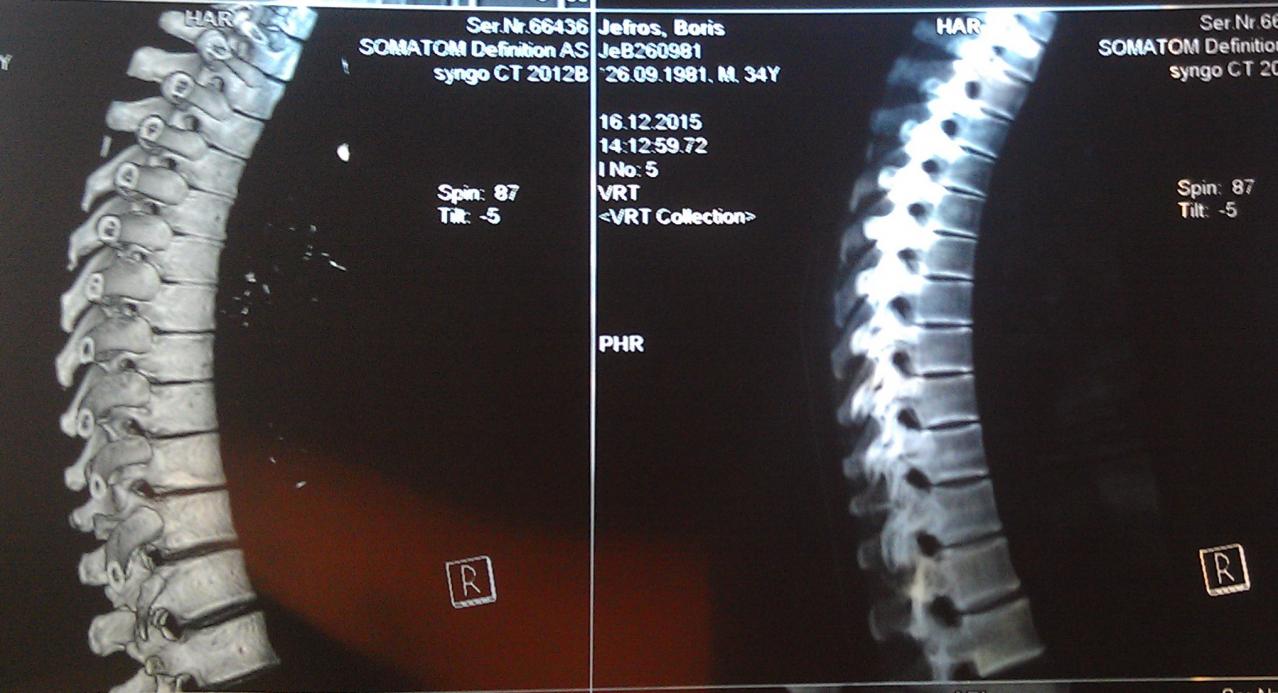

А достаточно ли плохих ревмопроб и компьютерной томограммы, где виден кифоз - чтобы поставить диагноз "болезнь Бехтерева"?

Вот моя компьютерная томограмма позвоночника.

Вложение 1182Вложение 1184Вложение 1185Вложение 1186Вложение 1183